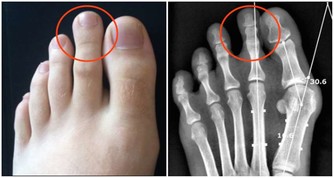

●如果你来大姨妈 女性由于每月一次的生理期失血,极易患轻度贫血,脸色苍白、面颊缺少红色,看起来无精打采,而且怕冷,常年手脚冰凉。多吃葡萄干,可以缓解手脚冰冷、腰痛、贫血等现象,提高免疫力。上班的女性不妨每天吃一小把葡萄干,连吃7天就能收到明显的效果,这个小偏方对治疗白带过多也有效。 ●如果你常感疲惫 葡萄干还含有多种矿物质和维生素、氨基酸,常食对神经衰弱和过度疲劳者有较好的补益作用。 ●如果你总觉气短(总要来几下深呼吸才舒服) 葡萄干铁和钙含量十分丰富,并有多种维生素和氨基酸,补血补气暖肾,治疗贫血、血小板减少,是儿童、妇女及体弱贫血者的滋补佳品。 ●如果你眩晕、心悸、乏力 葡萄干内含大量葡萄糖,可防眩晕、心悸、乏力等低血糖反应症状。